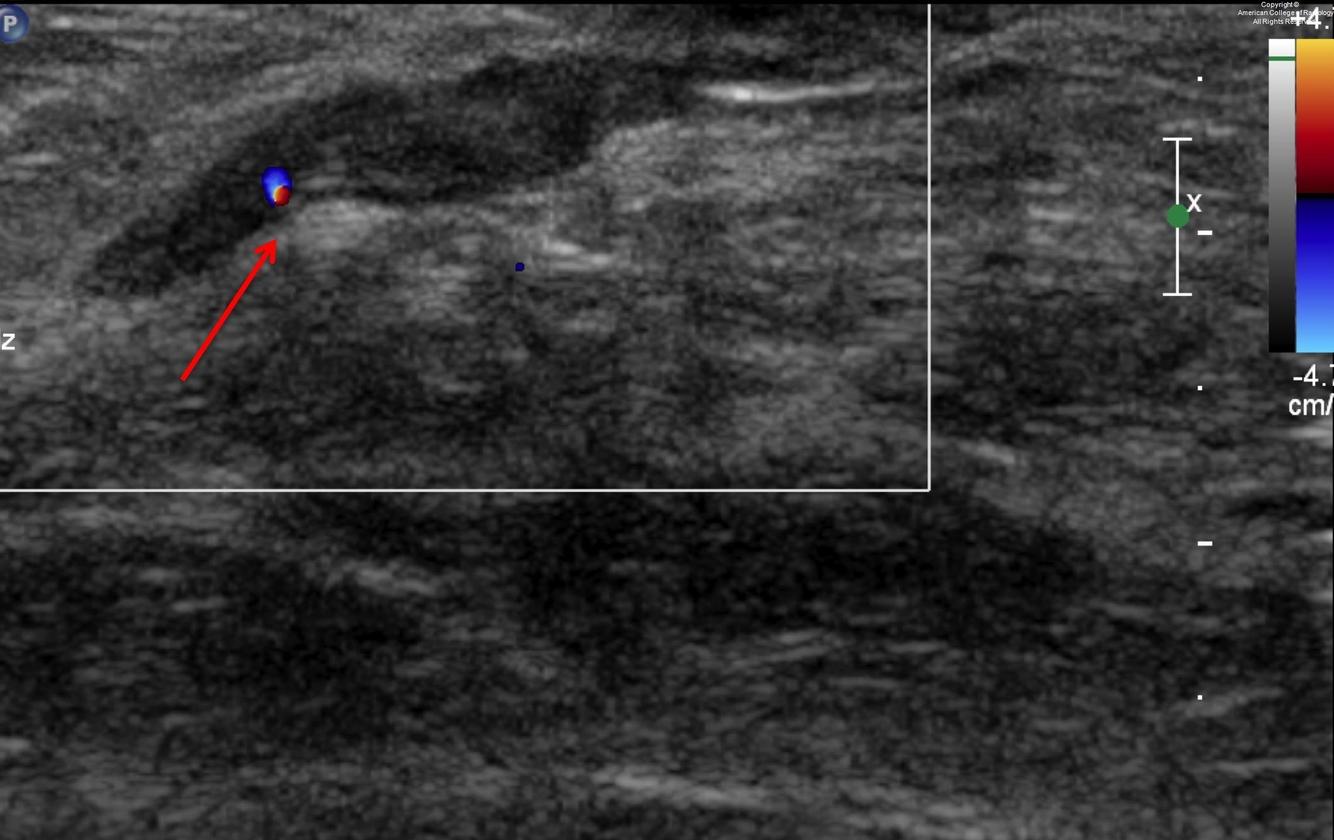

Dilated duct due to intraductal papilloma